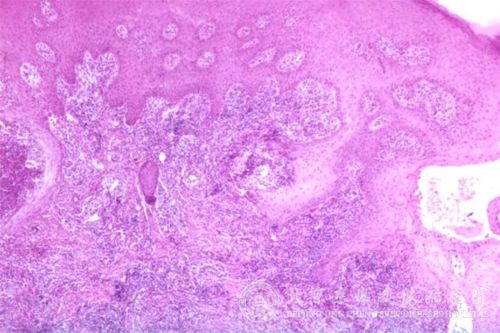

过敏性紫瘢的伴随症状与治疗都有什么?过敏性紫癜是常见的一种皮肤病,过敏性紫癜经常给人带来无尽的烦恼和痛苦,因此很多人会问这个问题。过敏性紫癜给人们的生活工作带来了严重的影响,因此及时了解过敏性紫癜的相关因素,可以有助于我们及早的发现过敏性紫癜以及治疗过敏性紫癜的皮肤症状。

过敏性紫瘢的伴随症状:病人可有胃肠道症状,如腹部阵发性绞痛或持续性钝痛等;可有关节疼痛;肾脏症状,如蛋白尿、血尿等,多见于儿童。